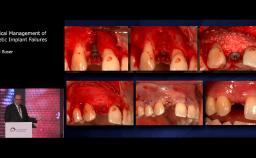

Patient expectations continue to increase, with the majority of patients expecting to have immediate replacement of missing teeth. This lecture provides a sound understanding of the key factors surrounding immediate implant placement. Advantages and disadvantages of this approach are discussed, using various cases to illustrate key points. Factors influencing esthetic outcome are discussed, with a good selection of evidence based information being presented.

describe the factors influencing success and failure of immediate implant placement

recognize the complexity of immediate implant placement

explain factors that influence esthetic outcome